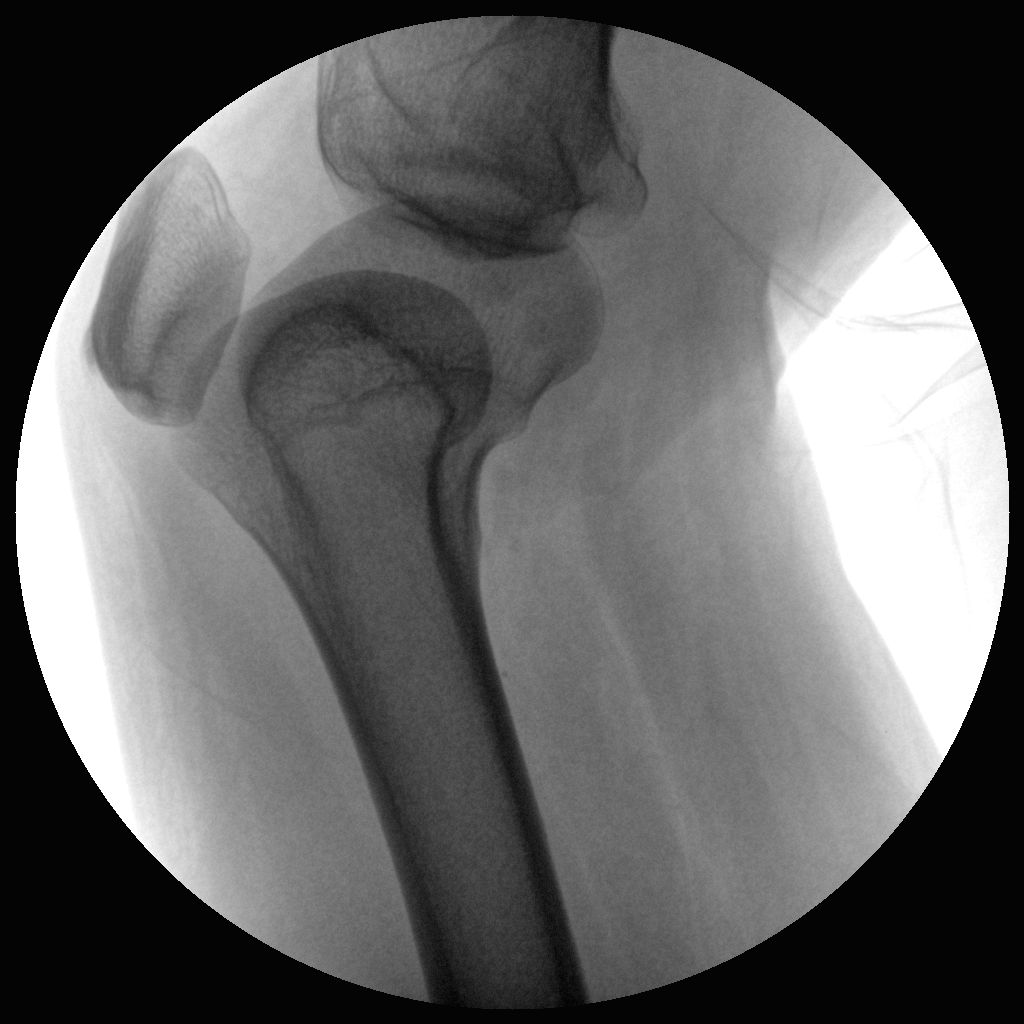

●全數(shù)字化百萬(wàn)像素影像系統(tǒng),圖像清晰